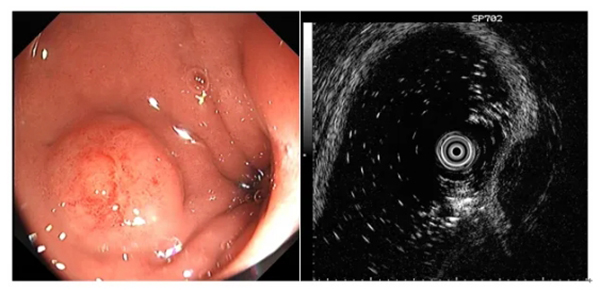

圖示超聲內(nei)鏡判斷(duan)黏膜下腫物(wù)性質(zhi)